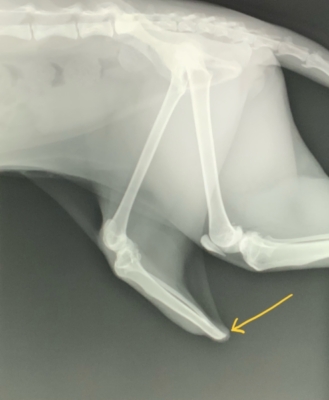

術前のレントゲン写真を下に示します。骨の断端がやや鋭利なのと、付着する組織が薄く、床についたりぶつけるとすぐ下に固い骨がある状態です。これは出血もしやすいし痛みも強いでしょう。下手すると外傷から骨への感染の可能性もあります。